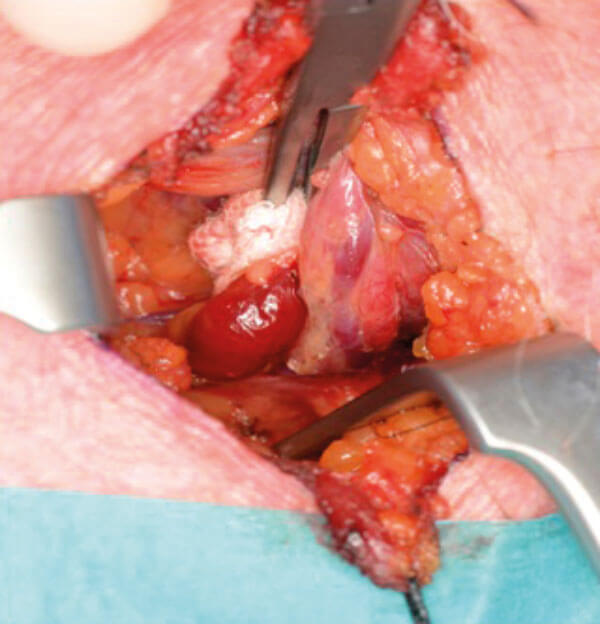

Figure 8 and 9. Minimal dissection required. Retraction of thyroid lobe to locate PT gland.

When the dissection has progressed to the stage of identifying the surface of the thyroid gland, the ruler can be used to measure the distance from posterior aspect of thyroid to where the targeted PT gland should be. Confirmation of cricoid distance may be used at this time to accurately pinpoint the adenoma. This is useful when starting to do this type of surgery.